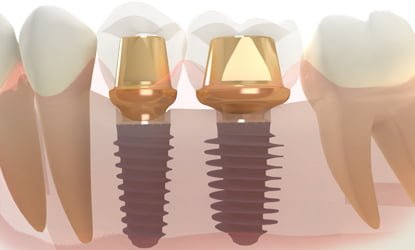

Trečias žingsnis —

Implanto atrama

Implanto atrama – jungiamoji dalis tarp implanto ir danties vainikėlio.

Implanto atrama yra priveržiama prie implanto po oseointegracijos arba priklausomai nuo pirminio implanto stabilumo. Kuo pirminis implanto stabilumas yra geresnis, tuo protezavimas gali prasidėti greičiau. Kuo implanto ir atramos jungtis yra tvirtesnė, tuo ilgaamžiškesnis yra protezavimas ir galutinio rezultato patvarumas.